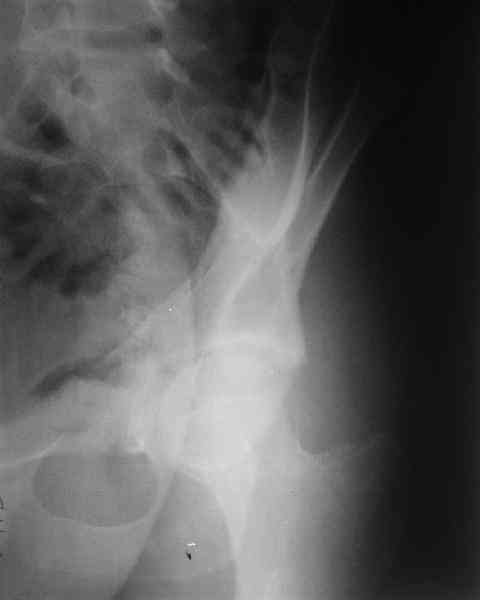

What is your indication for surgical management? What kind of fracture do you think it is? It looks like a transverse type although it has been a couple of years since I looked at an acetabular fracture.

The last two images from the 3-D CT scan certainly makes the fracture look worse than the plan radiographs.

Some more images. Does it help to guess which part of the acetabulum is displaced?

Normal appearing SI joints and a healed posterior column limb... my bet's on caudal segment displacement.